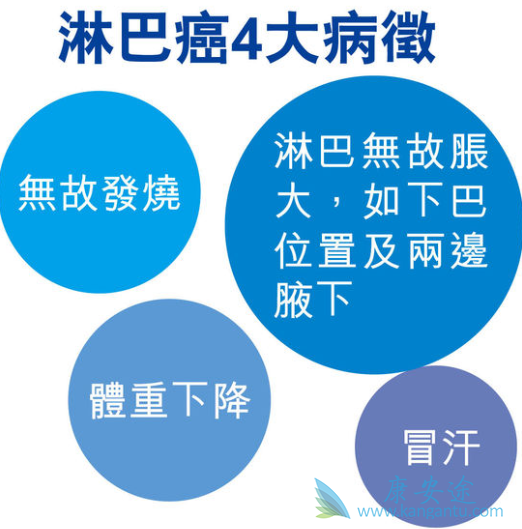

淋巴癌早期的6大警訊! | Heho健康

淋巴癌早期症狀有哪4點 – 每日頭條

淋巴癌已經開始「年輕化」 – 每日頭條

早期淋巴癌发病之后会有哪些症状?-康安途海外医疗